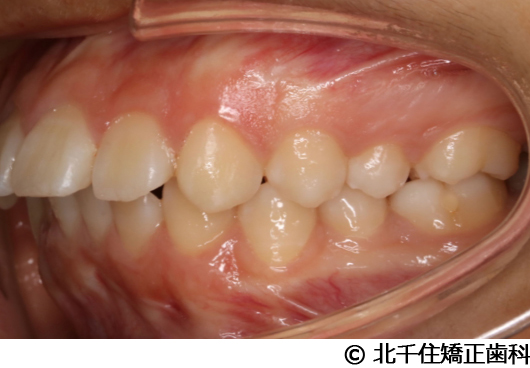

【症例3】叢生

- 治療前

- 治療後

- 治療名

- 叢生

- 費用

- 1,125,000円(税込)

- 期間

- 2年1ヵ月

- 治療回数

- 26回

- 通院頻度

- 1ヵ月ごと

- 年齢・性別

- 19歳3ヵ月・女性(初診時)

治療内容

主訴:デコボコ、口元の突出

上下顎第一小臼歯4本を抜歯してワイヤー矯正(セラミックブラケット)。

叢生に対し抜歯を併用した矯正治療により、歯列および咬合関係の調整を行った症例である。治療後は保定装置を使用し、歯列および咬合の安定維持を目的として定期的な経過観察を行っている。

※治療結果は個人差があります。

治療を行う上での注意点(リスク・副作用)

歯磨き不良に伴うカリエスや歯周病、歯根吸収など。